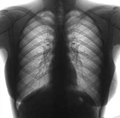

Украина заняла 5 место среди стран с наибольшим уровнем заболевания туберкулезом

Всемирная организация здравоохранения заявляет, что Украина заняла 5 место среди 27 стран с наибольшим уровнем заболевания туберкулезом. Об этом говорится в пресс-релизе представительства ВОЗ в Украине.

"ВОЗ определила 27 стран с наибольшим грузом туберкулеза, на которые приходится 85% общего количества случаев мультирезистентного туберкулеза. В этом перечне Украина занимает пятое место после Азербайджана, Молдовы, Казахстана и Узбекистана", - сказано в сообщении.

ВОЗ отметила, что в Украину с населением в 46,143 миллиона лиц (по состоянию на 1 января 2009 года) приходится 11% от всех зарегистрированных случаев туберкулеза в европейском регионе ВОЗ.

Согласно информации организации, ежегодно в мире заболевают свыше 8 миллионов и умирают около 2 миллиона лиц несмотря на то, что раннего выявления туберкулеза и прохождения полного курса лечения достаточно для полного выздоровления.